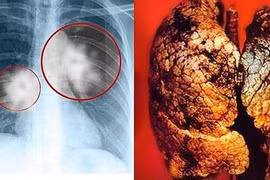

Ung thư có thể di căn đến hầu hết các bộ phận của cơ thể, một số tế bào ung thư thường di căn đến như xương, phổi, gan và não. Các triệu chứng liên quan đến sự hiện diện của các tế bào ung thư trong cơ quan nơi chúng lây lan.